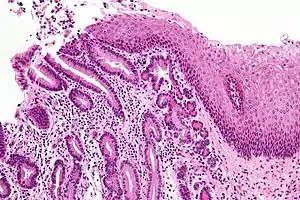

| Micrograph of a gastro-esophageal junction with pancreatic acinar metaplasia. The esophageal mucosa (stratified squamous epithelium) is seen on the right. The gastric mucosa (simple columnar epithelium) is seen on the left. The metaplastic epithelium is at the junction (center of image) and has an intensely eosinophilic (bright pink) cytoplasm. H&E stain. |